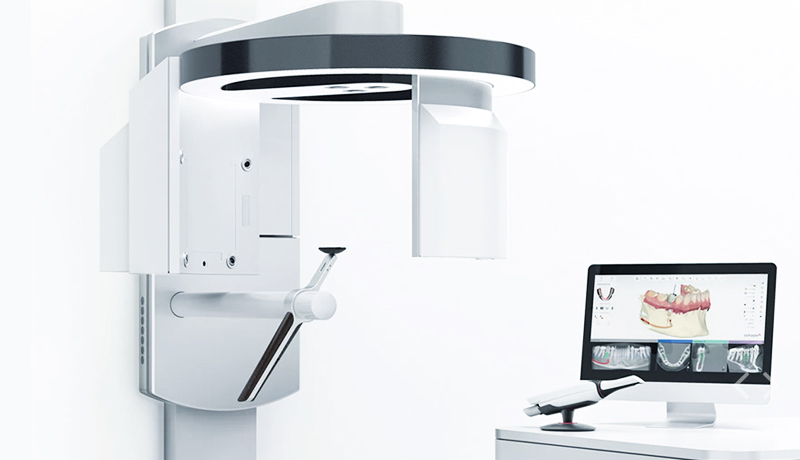

针对取模,您还愿意咬着藻酸盐吗?张口30分钟,流口水、恶心干呕,边缘不清晰,还要重头再来。麦芽口腔改物理取模为数字取模,3分钟完成单颌100万个数据点采集,同时重建数字化模型,为种植方案设计提供完整的三维数据。

数字化矫治系统2015年正式进入麦芽口腔

ClinCheck标志着麦芽初步实现数字化矫牙模拟,图像与影像数据的精确采集提取后,可由医生操作模拟矫牙的过程,矫牙方案不再靠“口述”与“想象”。

数字化智能3D口扫实时重建三维数据

一改传统物理取模为数字取模,激光探头舒适扫过,取模仅仅3分钟,除此,实时重建牙颌组织与咬合关系,让数据获取极简、智能、舒适。